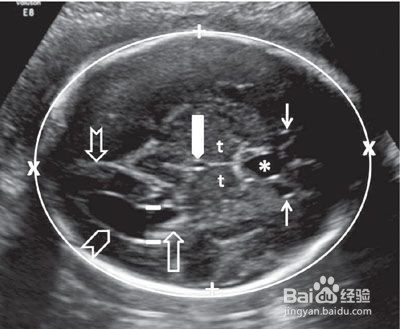

4、四:胎儿侧脑室增宽1.0cm之内

发育正常的胎儿侧脑室应该在1cm以下,当胎儿脑脊液过多时,就会造成侧脑室增宽,一般情况下在发育后期大多能够自己吸收。

可以隔几周再做b超,看增宽的情况是不是持续。如果侧脑室增宽太多,也有可能是脑积水。

如果怀疑是脑积水,可以在做B超的时候看看有没有脊柱裂的情况,因为那是脑积水症状之一,如果没有的话,胎儿应该就是健康的。孕妈适当减少喝水量,过两周复查即可。